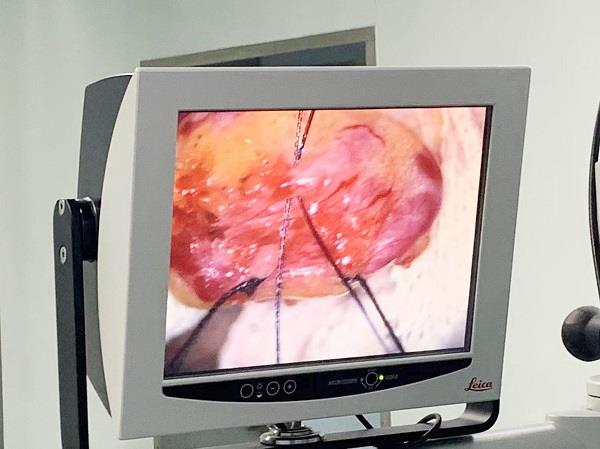

在安徽醫(yī)科大學(xué)第一附屬醫(yī)院男科幫扶專家、安徽省醫(yī)學(xué)會(huì)男科學(xué)分會(huì)主任委員張賢生教授指導(dǎo)下,由泌尿外科丁科主任醫(yī)師,金敦寅副主任醫(yī)師,孔維斌、車云飛主治醫(yī)師組成的手術(shù)組為患者成功實(shí)施“顯微鏡下精索靜脈結(jié)扎術(shù)”。患者術(shù)后恢復(fù)良好,目前已痊愈出院。

(圖片來源于網(wǎng)絡(luò))

目前手術(shù)治療有經(jīng)腹股溝管精索內(nèi)靜脈高位結(jié)扎術(shù)、腹腔鏡手術(shù)、經(jīng)腹膜后精索內(nèi)靜脈高位結(jié)扎、精索靜脈介入栓塞術(shù)、顯微鏡手術(shù)等。顯微鏡精索靜脈曲張手術(shù)主要就是在顯微鏡下做精索靜脈曲張結(jié)扎手術(shù)。這種手術(shù)通過顯微鏡的放大效果,可以清楚的發(fā)現(xiàn)精索曲張的靜脈,復(fù)發(fā)率非常低,并發(fā)癥特別少。顯微外科治療精索靜脈曲張,可以明顯的改善精液質(zhì)量,提高受孕的概率。其主要的優(yōu)點(diǎn)是能夠很清楚的結(jié)扎曲張的精索靜脈,保留其他的靜脈、動(dòng)脈、神經(jīng)、淋巴管,減少復(fù)發(fā),減少睪丸鞘膜積液、睪丸萎縮的發(fā)生。